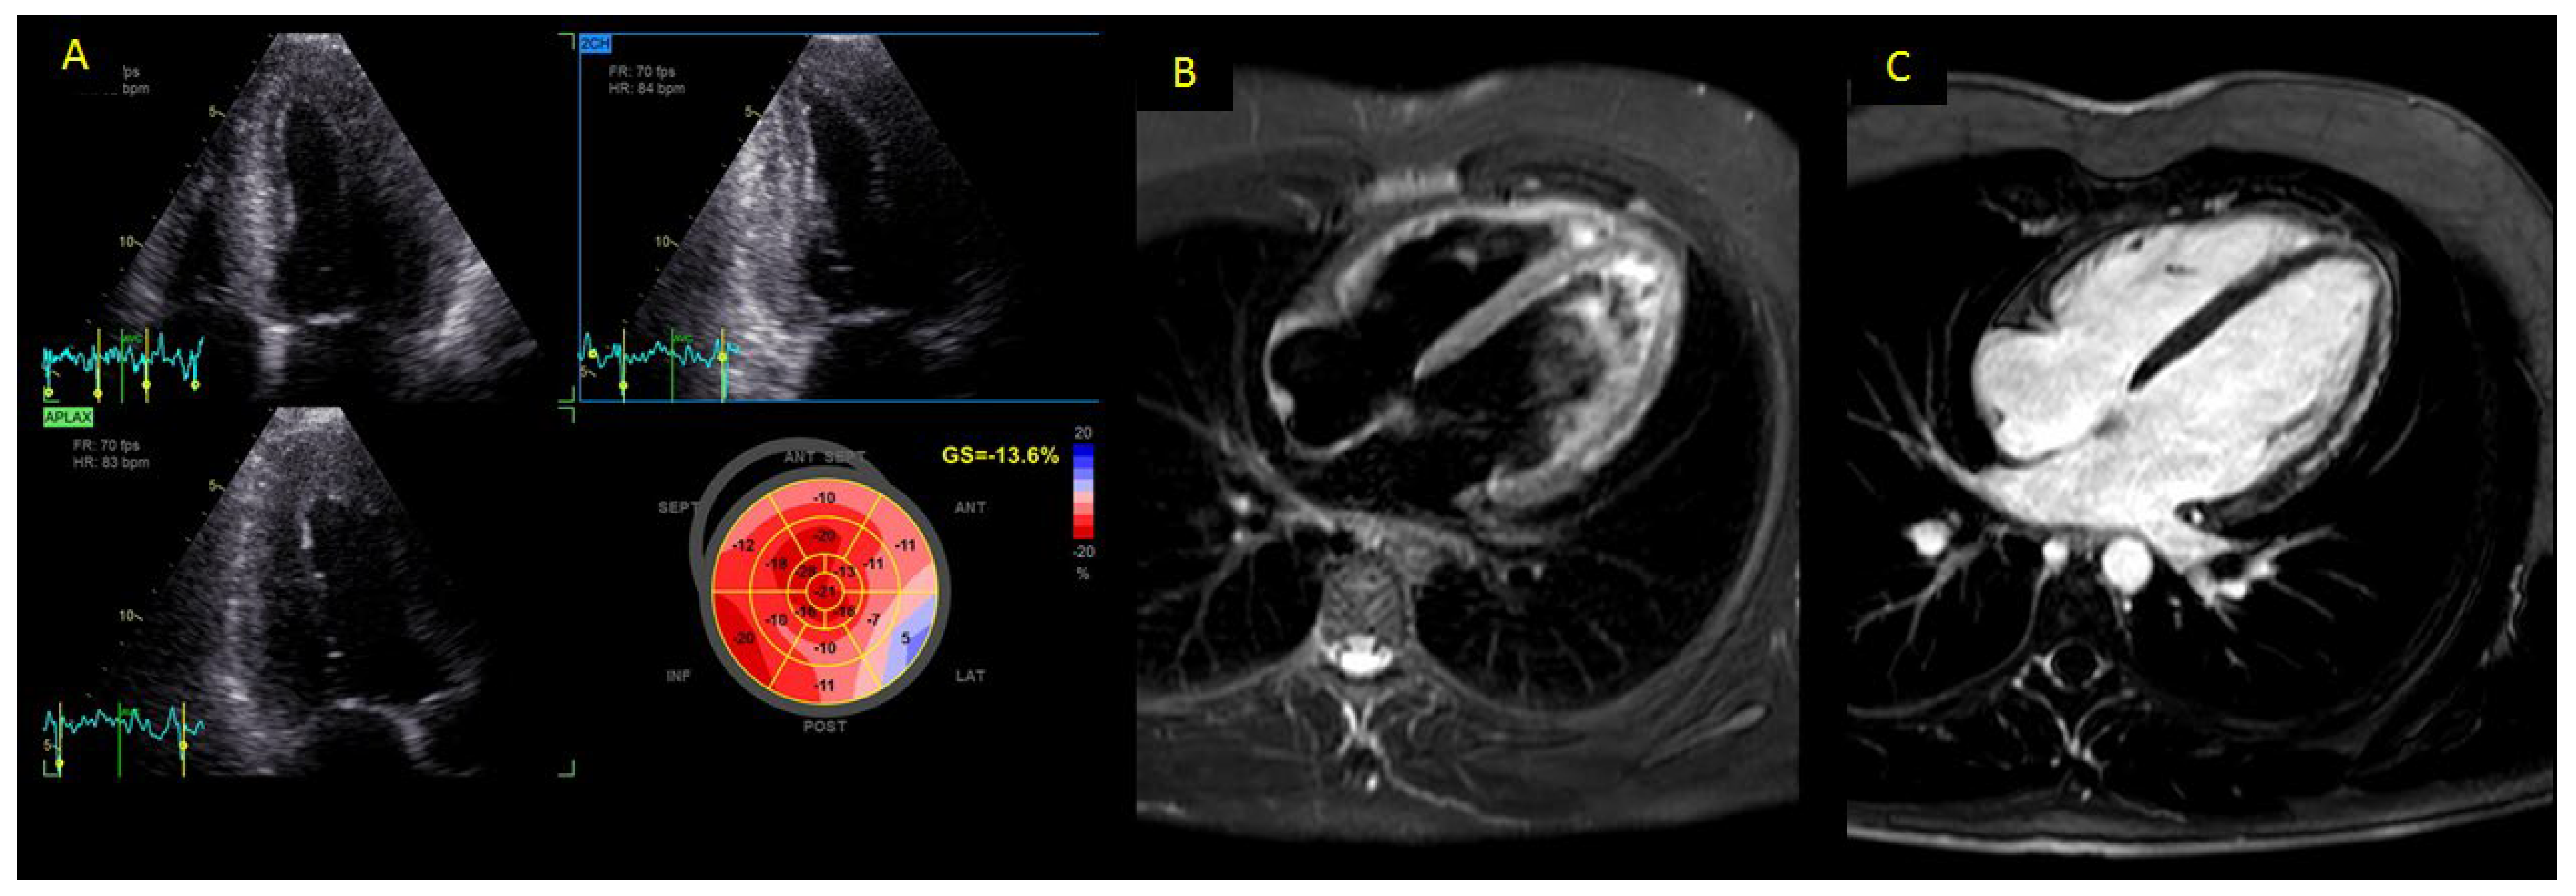

2.3. Standard Transthoracic 2-Dimensional (2D) and Speckle-Tracking Echocardiography (STE) Analyses

| Speckle tracking | GLS, % | −14.4 ± 5.2 | −22.1 ± 3.8 | ** |

| Epicardial GLS, % | −11.4 ± 5.8 | −21.4 ± 3.1 | *** | |

| Mid-wall GLS, % | −13.9 ± 4.3 | −22.4 ± 2.8 | ** | |

| Endocardial GLS, % | −15.9 ± 3.3 | −23.7 ± 4.8 | ** |